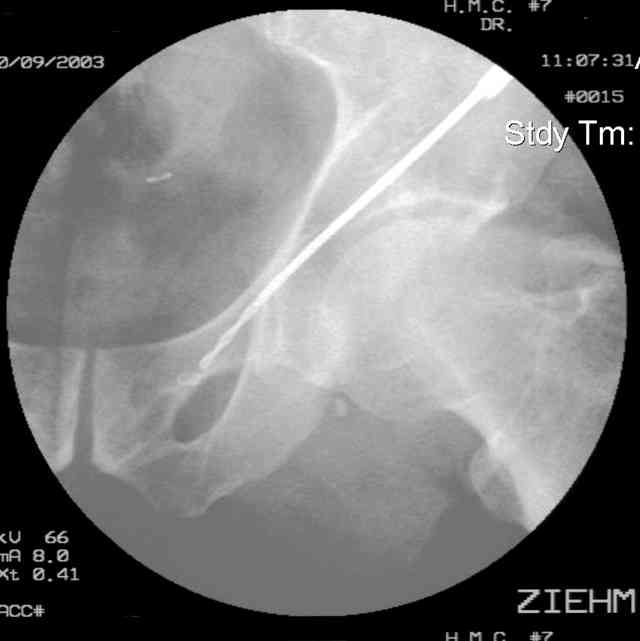

45 yo male in MVA, only other injury=small subarrachnoid bleed (neurologically fine, GCS never <14), with this transverse & associated posterior wall fx-dislocation 7/7

In skeletal traction thru distal femoral pin 40 lbs with decent reduction - except for the free fragments in the hip joint. ORIF planned for post-injury day 11.

Stabilize anterior column with fluoroscopically guided screw across this end of the transverse fx - As usual, after your reduction of the femoral head, the transverse fx became minimally displaced - slightly gapped without stepoff. I usually (reduce &) stabilize the medial side of the posterior column (transverse fx) with a short plate - before placing the anterior screw unless the transverse fx is undisplaced.

Biggest problem appears to be impaction & comminution of the posterior wall fx site - you've left out some CT cuts. This is not just fragments in joint. It may leave a deficient area, &/or block satisfactory posterior wall reduction.